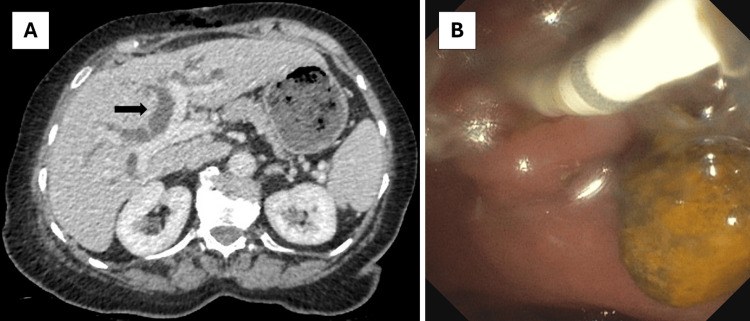

A diagnosis of chronic diarrhoea due to a CCF was made, and the patient was referred for cholecystectomy. One month later, she underwent a laparoscopic cholecystectomy with wedge resection of the fistula complex. The resection specimen showed chronic cholecystitis without dysplasia or carcinoma and confirmed the presence of a CCF. The patient was discharged in a stable condition the next day but was readmitted two days later because of fever, pronounced cholestasis, and dilatation of intra- and extrahepatic bile ducts on a CT performed at the emergency department (Figure 2). Intravenous ceftriaxone was started for acute cholangitis, and the patient was booked on the next available endoscopic retrograde cholangiopancreatography (ERCP) list two days later. This revealed a large stone in the common bile duct (CBD), which was extracted after sphincterotomy with spontaneous drainage of purulent liquid afterwards (Figure 2). The patient had a swift clinical recovery and was discharged home two days later. Follow-up at the outpatient clinic one month after surgery showed marked improvement in diarrhoea and quality of life.